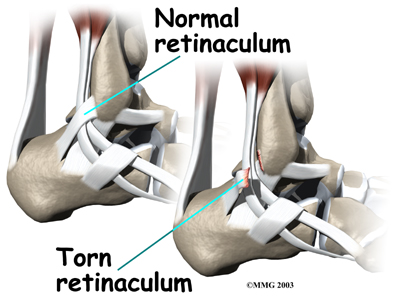

The tendons of the peroneal muscles pass together through a groove behind the lateral malleolus. The tendons are kept within the groove by a sheath that forms a tunnel around the tendons. The surface of this sheath is reinforced by a band of ligament called a retinaculum. Contracting the peroneals makes the tendons glide in the groove like a pulley. This pulley action points the foot downward (plantarflexion) and outward (eversion).

Tendons attach muscles to bone. Tightening a muscle puts tension on the tendon, which can move bone. Many tendons in the body are held in place by supportive connective tissue, such as a ligament or retinaculum. If the supportive tissue has been , the tendon may be free to slip out of its normal position. This is called . When the subluxed tendon slips back into place, this is called relocating. A tendon that forcefully snaps out of position and can't relocate has dislocated.

The main cause of peroneal tendon subluxation is an ankle sprain. A sprain that injures the ligaments on the outer edge of the ankle can also damage the peroneal tendons. During the typical inversion ankle sprain, the foot rolls in. The forceful stretch on the peroneals can rip the retinaculum that keeps the peroneal tendons positioned in the groove. As a result, the tendons can jump out of the groove. The tendons usually relocate by snapping back into place.

The injury to the retinaculum may be overlooked at first while treatment focuses on the injury to other ankle ligaments. This means the subluxation may begin much later, and it may not seem to be caused by the initial ankle sprain. If not corrected, this snapping of the tendons can become a chronic and recurring problem.

An acute dislocation of the peroneal tendons is rare. It occasionally happens during sport activities that force the foot up and in, for example during skiing, ice skating, or soccer. At the moment the foot turns up and in, the peroneals violently contract to protect the ankle. This can cause the retinaculum to tear, allowing the tendons to slip out of the groove.